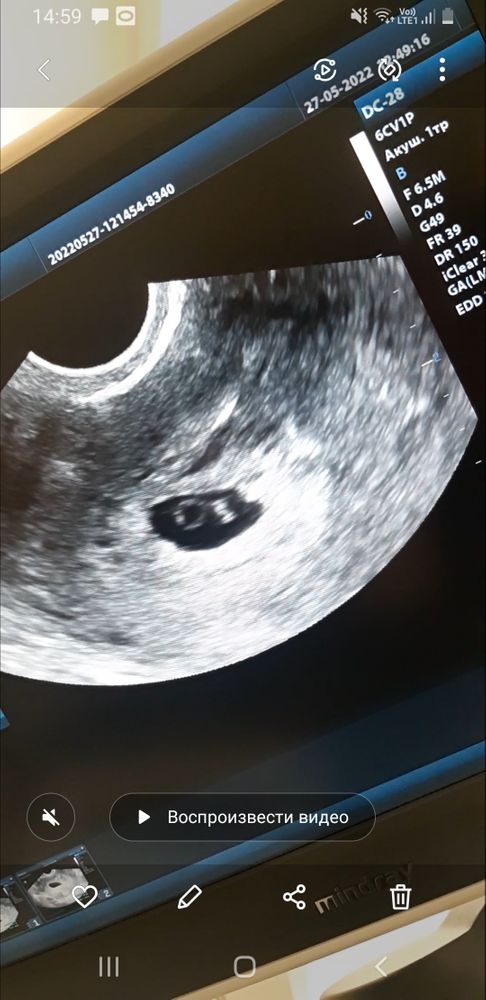

Была на УЗИ. По УЗИ срок 6 недель и 4 дня . Увидела как бьется сердце ❤ это чудо ! Врач сказала что все в норме , и теперь ждем скрининг.

Наталья Садкова, спасибо! Но я не слышала. Только видела сокращения. Сюда видео не могу добавить. Аппарат не берет сердце на таком раннем сроке . В итоге просто видно эмбрион и как сокращается сердце. 114 ударов